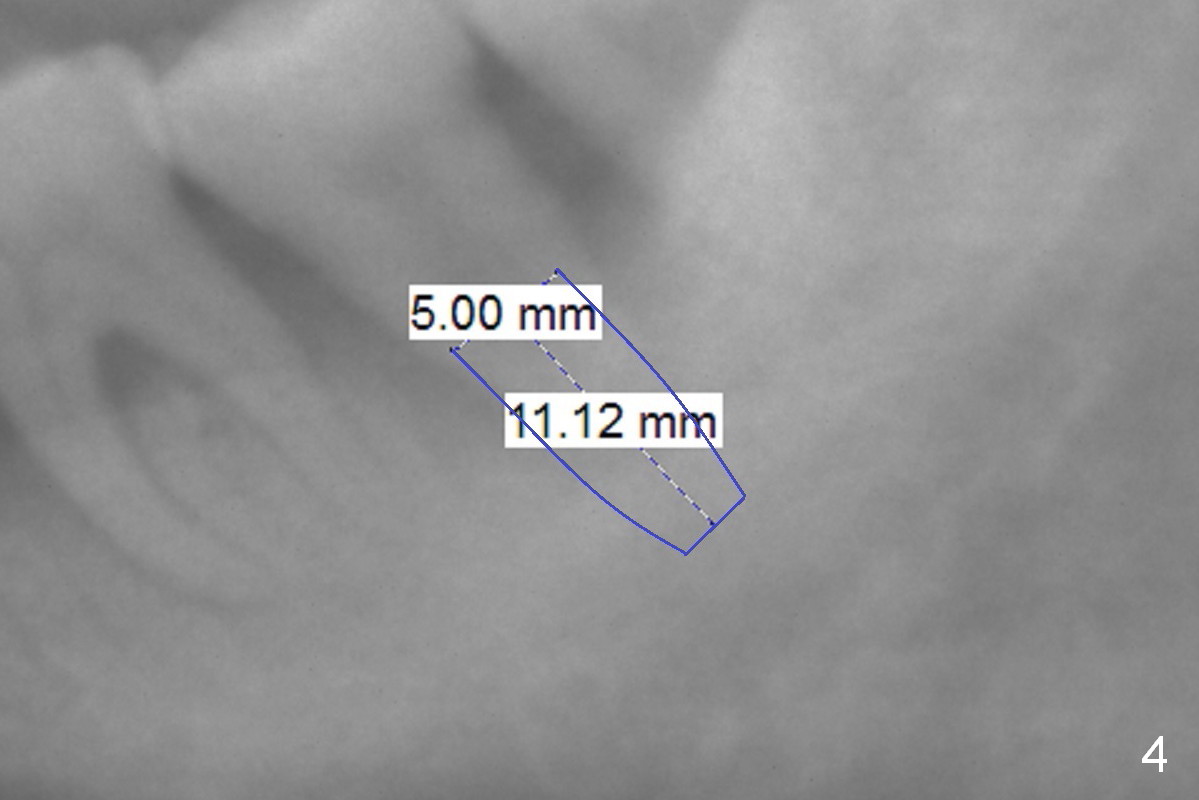

The teeth #14 and 18 of a 46-year-old man become symptomatic 1 month after #4 implant placement. While the socket at #14 is shallow, the apical bone is abundant (Fig.1). The longest IBS implant should be safe (13 mm, Fig.2). In contrast, the socket at #18 is relatively deep, the apical bone is short (Fig.3). A shorter implant (11 mm or less, Fig.4) should be chosen. Osteotomy in the new bone should be 4 mm. Try in a 5x9 mm dummy implant at #18. No antibiotic is used for socket treatment. The bone density in the mandible should be high (drills), whereas that in the maxilla may be low (expanders) or medium (drills). Preop exam will decide which tooth needs treatment first. Take photos PRN.